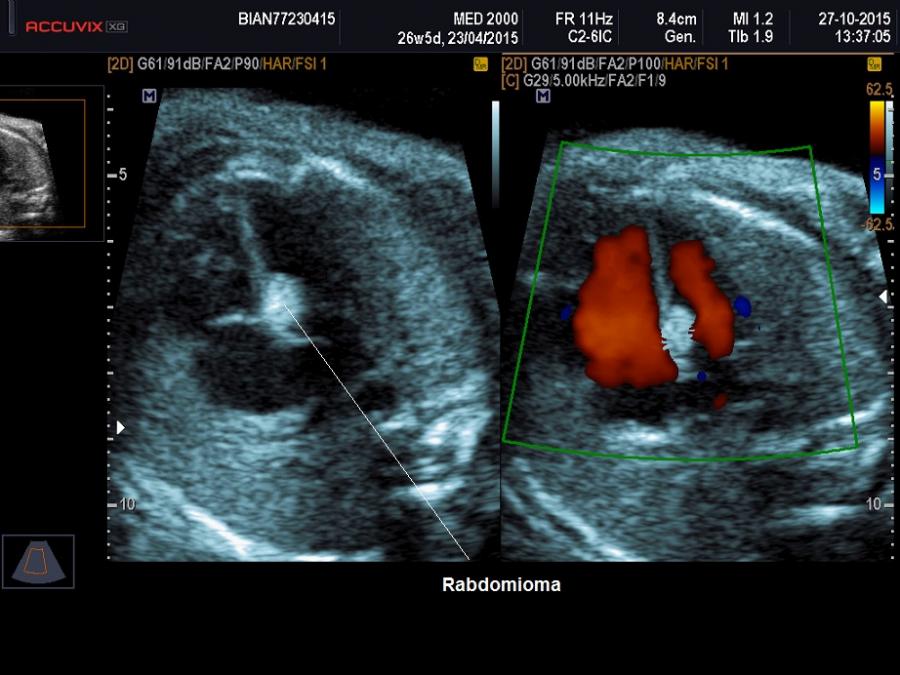

Rabdomioma: è la forma tumorale più

frequente rappresentando il 62% dei casi e nel 90% dei casi è multiplo. Si localizza nel contesto del setto interventricolare o può originare dalle pareti ventricolari. L'ecostruttura è iperecogena rispetto al miocardio e omogenea,

le dimensioni sono variabili. L'emodinamica cardiaca può essere modificata in

relazione al numero, alla localizzazione ed al volume dei tumori. Possono

determinare stenosi valvolare o aritmie che possono evolvere in idrope fetale. Può essere presente polidramnios.

calcificazioni e/o aree cistiche. Nel feto il riscontro di una massa intracardiaca orienta statisticamente verso la diagnosi di rabdomioma, specie se la lesione è multipla. Una caratteristica patognomonica, in caso di interessamento del setto ventricolare del rabdomioma, è il fatto che questo tipo di tumore coinvolge entrambi i lati del setto.